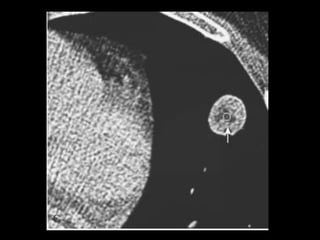

Atelectasia Redonda Forma de colapso pulmonar periférico não segmentar que pode simular um câncer primário de pulmão; Sempre encontrada a uma área adjacente de espessamento pleural; Processo parece se iniciar com uma efusão pleural adesiva ou uma reação pleural que encarcera o pulmão atelectasiado adjacente; Relação com asbesto.

• 82.

Atelectasia Redonda Esse pseudotumorpulmonar pode ser diferenciado: 1. Massa arredondada ou acunhada que forma ângulo agudo com a pleura; 2. Sinal da cauda de cometa; 3. Broncograma central visível na porção central da massa; 4. Realce homogêneo pelo contraste; 5. Redução no volume do hemitórax ipsilateral. OBS: biópsia ou ressecção.